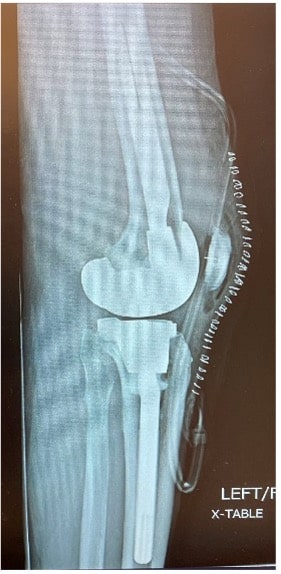

At the 6-week postoperative clinical exam, the x-rays showed good positioning of implants (Figures 5 and 6). The patient was doing well showing great signs of pain relief with increased stability and function.